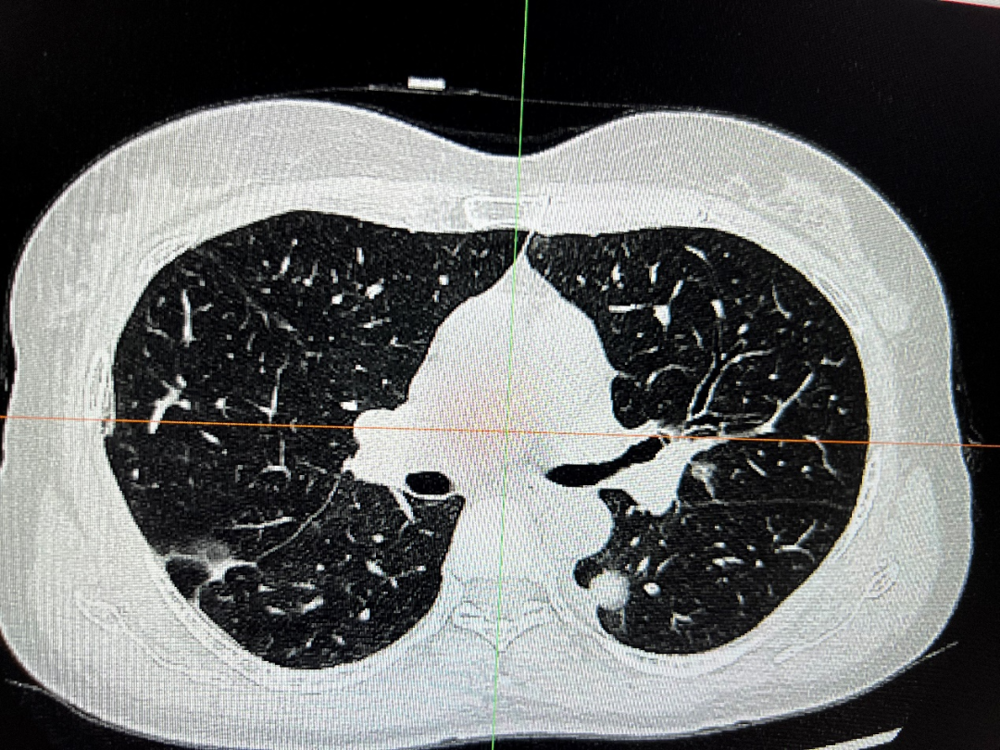

病例一: 雙側肺(fèi)癌(ái)同時(shí)手術病例患者,黎xx,女,55歲,發現肺部陰影(yǐng)2周(zhōu)入院。查體:生命體征平穩,心肺無(wú)明顯異常。輔助檢查:我院頭顱全腹部及(jí)胸部增強CT示:1、右肺上葉部分實性腫塊並兩肺多發部分實性、實性及磨玻璃結節,增強呈輕支中度強化,考(kǎo)慮右肺上葉肺Ca並肺內多(duō)發轉移可能,不排外非特異性感染(rǎn)或其他病變,建議纖維支氣管鏡及活檢(jiǎn)或穿刺檢查;兩肺少許纖維條索灶。2、顱腦、腹(fù)部、盆腔CT平掃未見明顯異常。診斷為雙肺多發性肺癌入院。患者有肺(fèi)結核病史,主病(bìng)灶在右肺上葉,次病灶在左肺下葉背段,為複雜手術。左側(cè)病(bìng)灶考慮原發性肺癌。術前與影(yǐng)像科及(jí)其麻醉科反複交流,患者身體條件尚(shàng)可,肺功能正常。術前決(jué)定行單孔胸腔(qiāng)鏡下雙側肺癌手術(shù)(胸腔鏡下(xià)右肺上葉切(qiē)除+左下肺背(bèi)段切除+雙側縱膈淋巴清掃)。術(shù)中在(zài)麻醉科周迎(yíng)春主任及蘭丙豐(fēng)醫師(shī)的大力支持下,保(bǎo)證患者在雙側(cè)手術過程中,生命體征穩定。術後安全(quán)返回病房,患者無(wú)疼痛等不適(術中打了肋間神經阻滯)。武寧縣人民醫院胸外科正式進入肺段切(qiē)除(chú)時代。

術前胸部CT

術中腫瘤位置